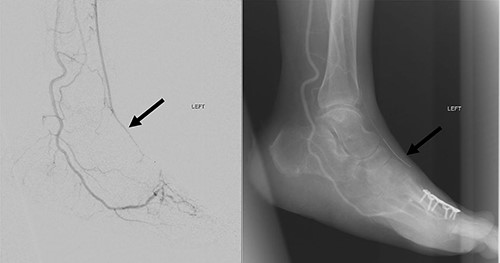

At 4 weeks post-operative date, her wound/flap has fully healed. She was then allowed full weight bearing over her left lower limb. At 3 months post-operative date, flap was fully healed, and her left lower limb remained well vascularized (Fig. 8).

Three-month post-operative, flap is fully healed and left foot remains well vascularized with palpable dorsalis pedis pulse.